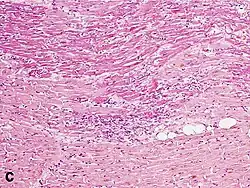

Under the microscope, myocardial infarction presents as a circumscribed area of ischemic, coagulative necrosis (cell death). On gross examination, the infarct is not identifiable within the first 12 hours.[20]

Although earlier changes can be discerned using electron microscopy, one of the earliest changes under a normal microscope are so-called wavy fibers.[21] Subsequently, the myocyte cytoplasm becomes more eosinophilic (pink) and the cells lose their transversal striations, with typical changes and eventually loss of the cell nucleus.[22] The interstitium at the margin of the infarcted area is initially infiltrated with neutrophils, then with lymphocytes and macrophages, who phagocytose ("eat") the myocyte debris. The necrotic area is surrounded and progressively invaded by granulation tissue, which will replace the infarct with a fibrous (collagenous) scar (which are typical steps in wound healing). The interstitial space (the space between cells outside of blood vessels) may be infiltrated with red blood cells.[20]

These features can be recognized in cases where the perfusion was not restored; reperfused infarcts can have other hallmarks, such as contraction band necrosis.[23]